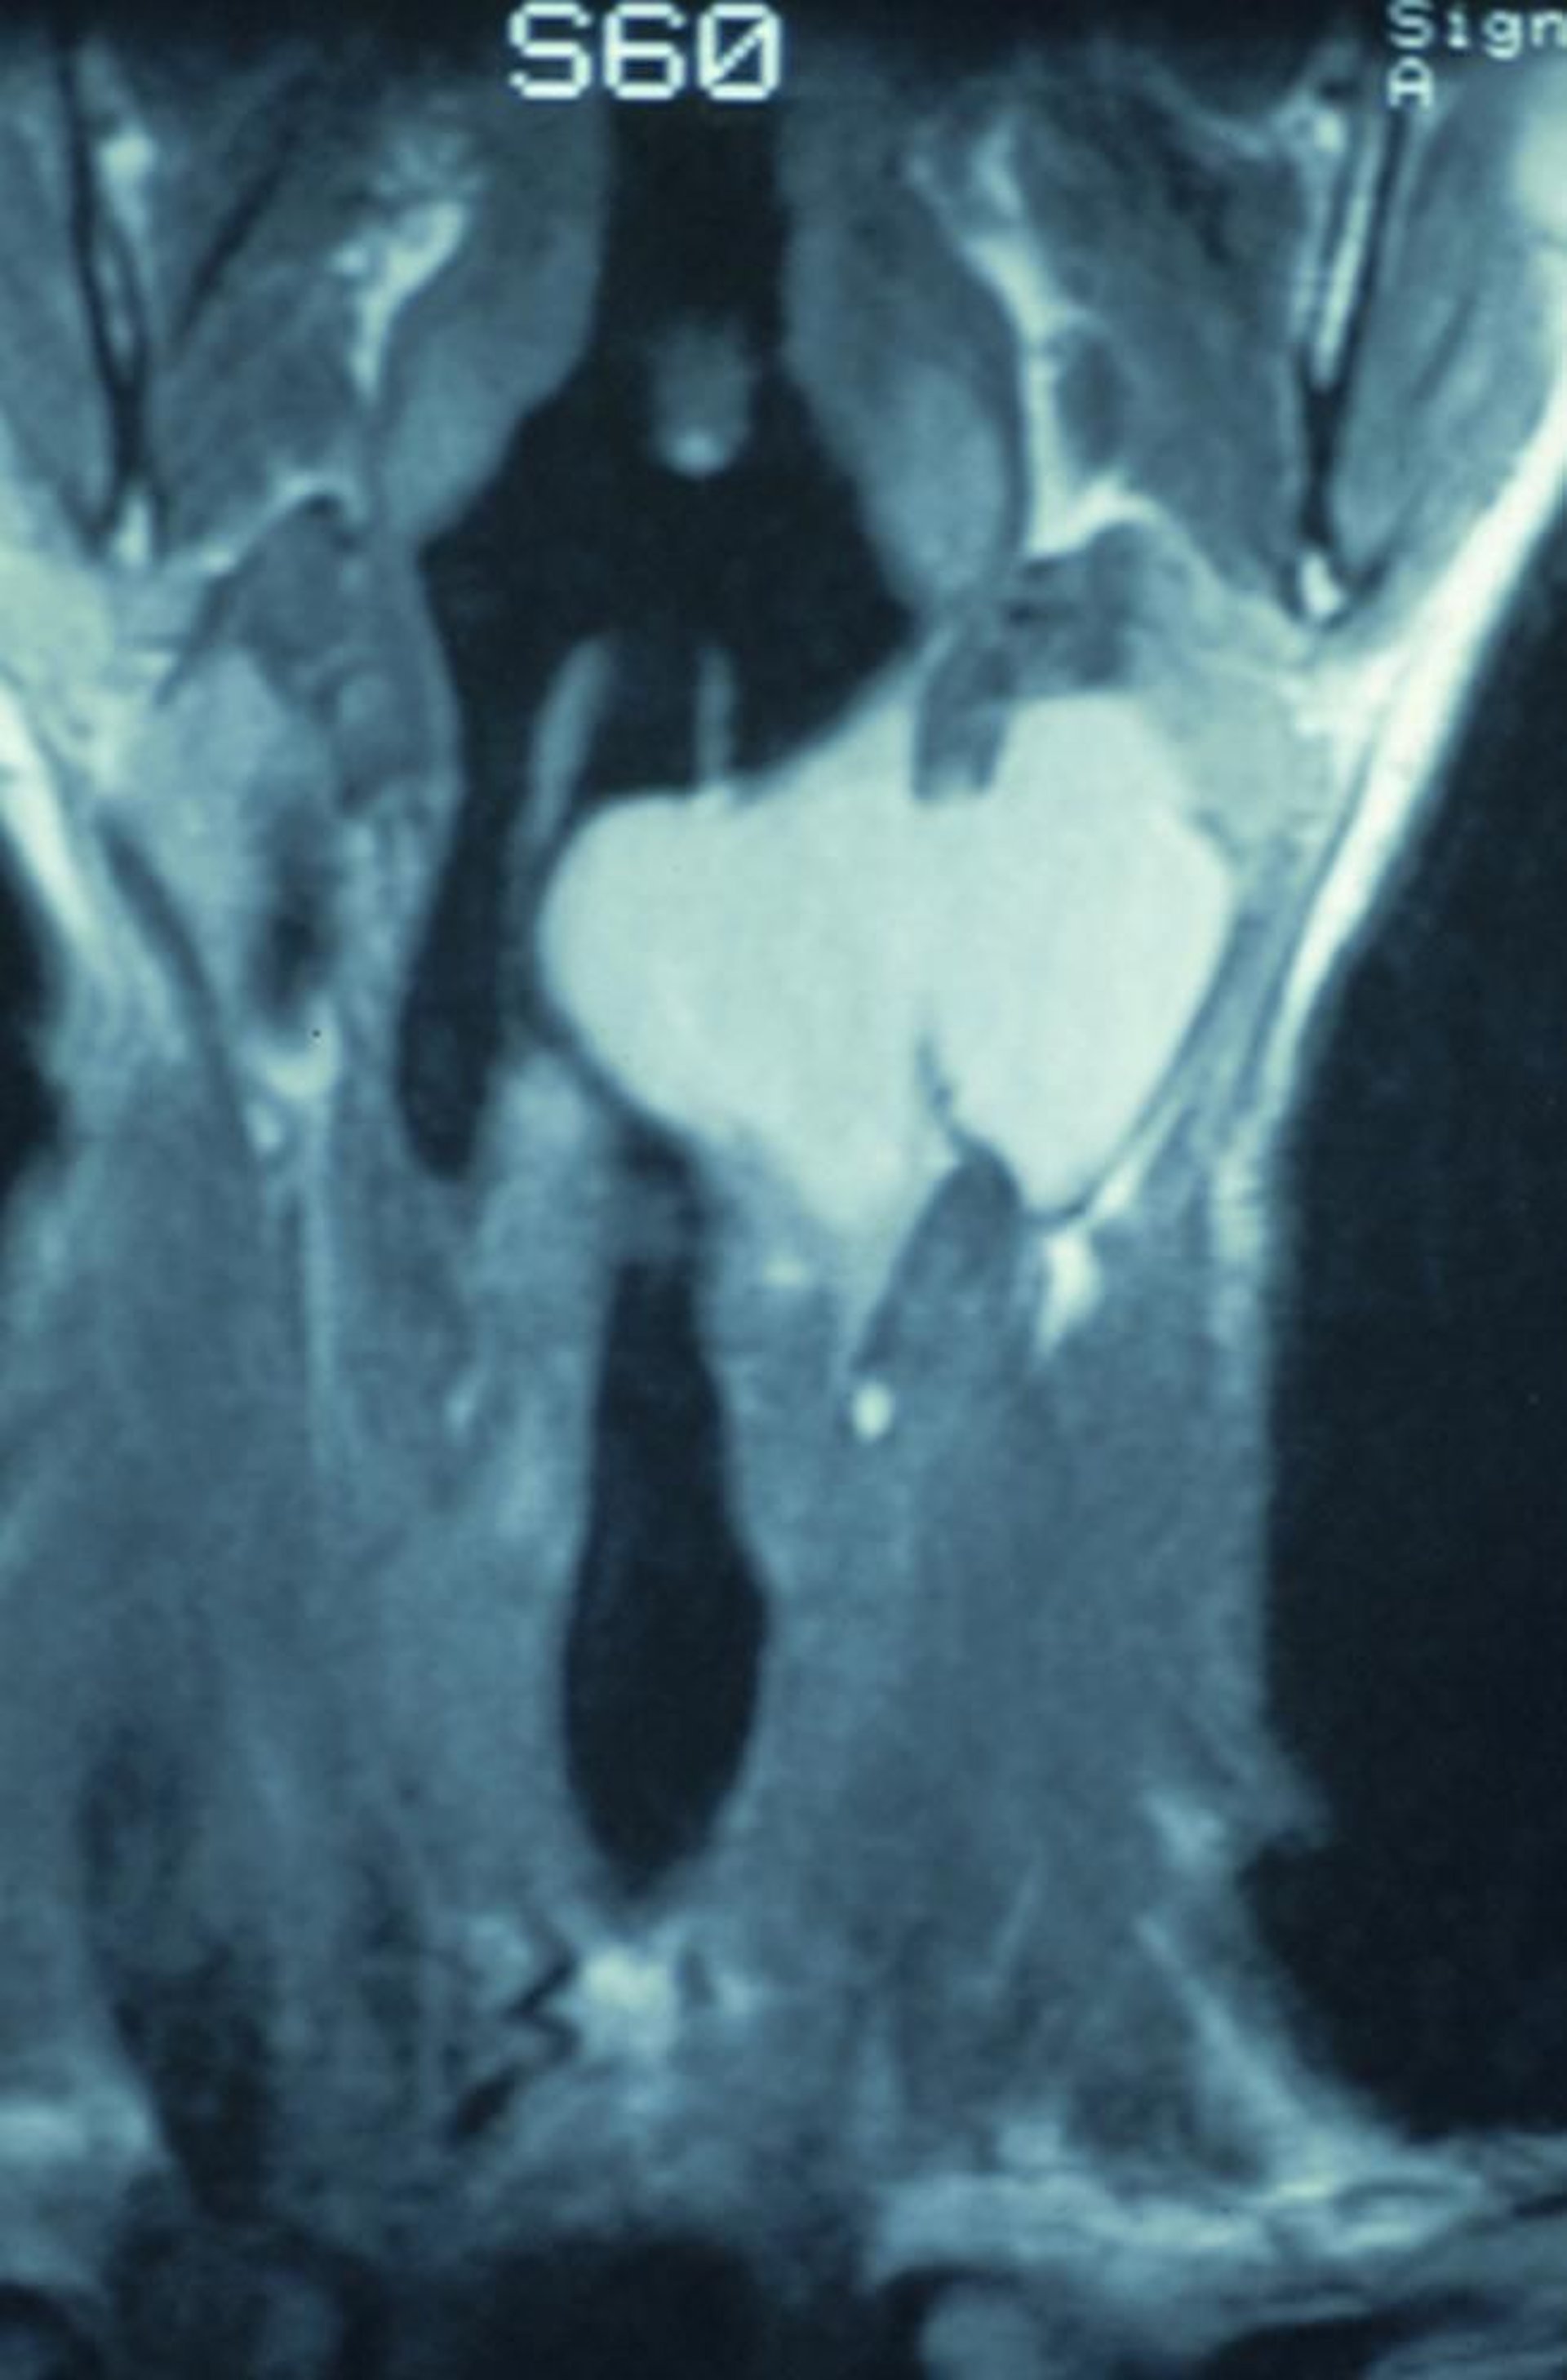

Laringocele misto

Questa scansione TC coronale mostra un laringocele misto che inizia all'interno della laringe e si estende attraverso la membrana tiroioidea, causando una massa nel collo.

Image provided by Clarence T. Sasaki, MD.